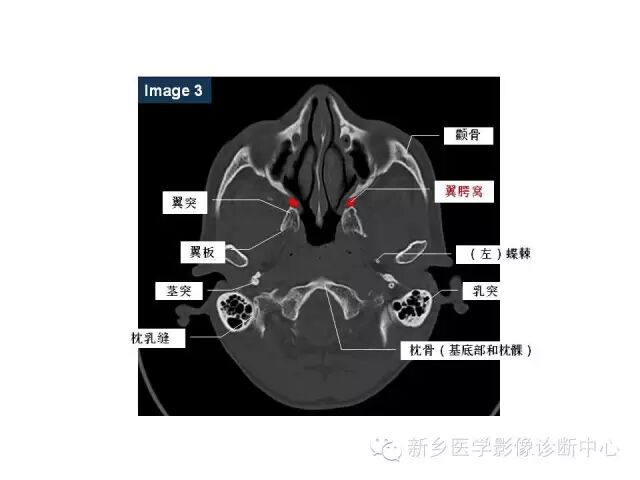

鼻咽部的详细解剖(含各个孔道)

来源:新乡医学影像诊断中心